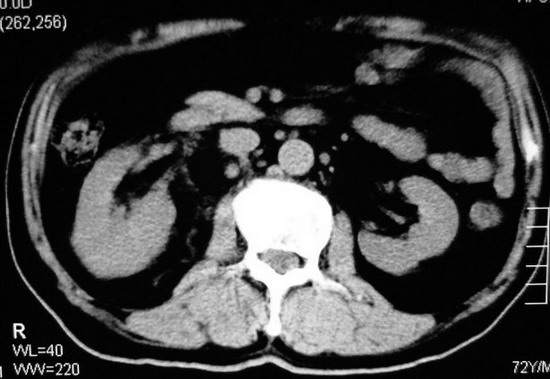

以下是引用杀毒软件在2008-11-17 19:15:00的发言:[br]考虑------右肾癌合并肾静脉---同侧肾上腺受侵可能性大

以下是引用zjzjr在2008-11-17 20:45:00的发言:[br]考虑------右肾癌合并肾静脉---同侧肾上腺受侵可能性大及腹膜后淋巴结转移.